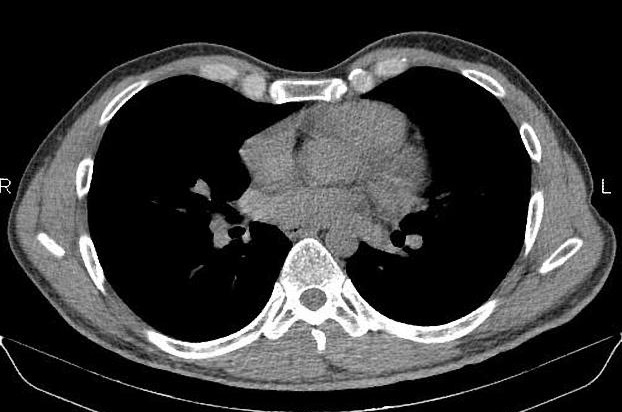

Même cas en coupe TDM axiale . Metastase

costale |

La

TDM et IRM être faciliter le diagnostic

topographique tumoraux et la présence ou non du

liseré graisseux. La TDM ou IRM avec injection de

produits de contraste se donne de déduire des gammes

étiologiques pafaite :

Les opacités pleurales

dues aux épanchements sont habituellement en «

goutte » avec raccordement obtus en haut et aigu en

bas. Quand ils ne sont pas évidents en standard, ils

sont affirmés en TDM par le signe du « split pleura

»: le produit de contraste souligne la division des

deux feuillets pleuraux viscéral et pariétal, autour

de l'empyème. La distinction avec l'abcès pulmonaire

(sphérique et avec bronchogramme) est aisée

Les tumeurs

pleurales localisées sont plus difficiles à

distinguer du syndrome pariétal que les épanchements.

Les tumeurs à origine de la plèvre pariétale sont

mal différenciées avec syndrome pariétal, d'autant

qu'elles peuvent éroder la côte et donc créer un

syndrome pariétal « secondaire ». C'est le cas des

mésothéliomes malins débutants, non encore

circonférentiels mais pouvant localement

|